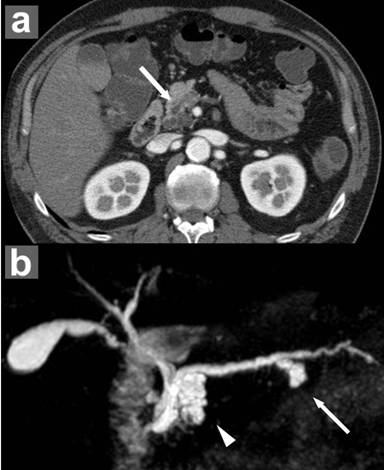

A 55-year-old Japanese male patient was admitted to our hospital for detailed examination of cystic lesions in the pancreas. He had neither a past history of diabetes mellitus nor a family history of malignancy, including PDAC. Physical examination showed no abnormalities. Laboratory examination revealed slight elevation of the serum carcinoembryonic antigen (CEA) level (4.3 ng/mL; reference range: 0-2.5 ng/mL at our institution), while the carbohydrate antigen (CA) 19-9 level (0.6 IU/mL) was within normal limits (reference range: 0-37 IU/mL). Enhanced CT and MRCP demonstrated multilocular cystic lesions in the pancreas head (25 mm in diameter) and body (16 mm in diameter) (Figure 1). Endoscopic ultrasonography (EUS) showed multiple branch duct IPMNs without findings suspicious for a mural nodule. Endoscopic retrograde pancreatography (ERP) showed a dilated duodenal papilla orifice caused by mucus hypersecretion and revealed that the cystic lesions in the pancreas head and body communicated with the main pancreatic duct; however, no irregularity of the main pancreatic duct itself was noted (Figure 2a). Subsequent peroral pancreatoscopy showed a fish egg-like appearance at the orifice of the dilated branch duct in the pancreas head, and pancreatic juice cytology revealed class V, highly suggestive of adenocarcinoma (Figure 2b).

Figure 1. Preoperative enhanced computed tomography (CT) and magnetic resonance cholangiopancreatography (MRCP). a. Enhanced CT shows a 20-mm diameter multilocular cystic lesion in the head of the pancreas (arrow). b. MRCP also shows a multilocular cystic lesion in the head of the pancreas (arrowhead) and a unilocular cystic lesion in the body (arrow), indicating multiple branch duct IPMNs. |